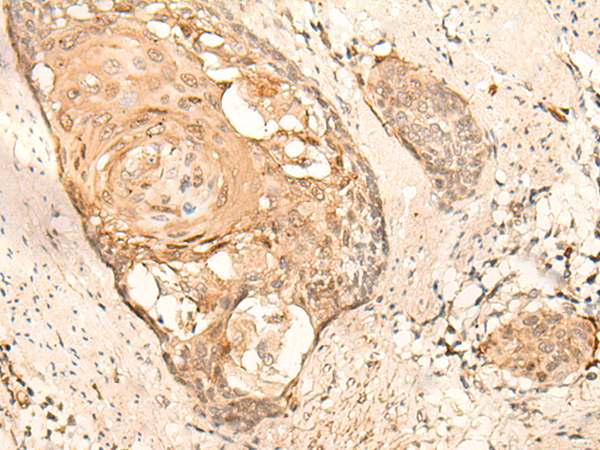

IHC positive control: |

Human esophagus cancer and Human breast cancer |